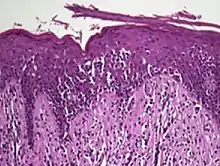

| Skin lesions on the knee of a 52-year-old male patient with Mycosis fungoides | |

Histology

The criteria for the disease are established on the skin biopsy by the presence of the following:[18]

- Presence of cancer cells with twisted contours (cerebriform nuclei)

- In the patch and plaque stages, the cancer cells are seen in the epidermis (the most superficial layer of skin).[19] This is referred to as epidermotropism.

- Pautrier's microabcesses, aggregates of four or more atypical lymphocytes arranged in the epidermis. Pautrier microabcesses are characteristic of mycosis fungoides but are generally absent.

- In the tumour stage, the cancer cells move into the dermis (the deeper layer of skin)[19]

- Large cell transformation, where clonally identical lymphocytes in the lesion exhibit hypertrophy. In transformed cells, presence of the CD30 receptor is associated with improved survival[20]

Traditionally, mycosis fungoides has been divided into three stages: premycotic, mycotic and tumorous. The premycotic stage clinically presents as an erythematous (red), itchy, scaly lesion. Microscopic appearance is non-diagnostic and represented by chronic nonspecific dermatosis associated with psoriasiform changes in epidermis.

In the mycotic stage, infiltrative plaques appear and biopsy shows a polymorphous inflammatory infiltrate in the dermis that contains small numbers of frankly atypical lymphoid cells. These cells may line up individually along the epidermal basal layer. The latter finding if unaccompanied by spongiosis is highly suggestive of mycosis fungoides. In the tumorous stage a dense infiltrate of medium-sized lymphocytes with cerebriform nuclei expands the dermis.